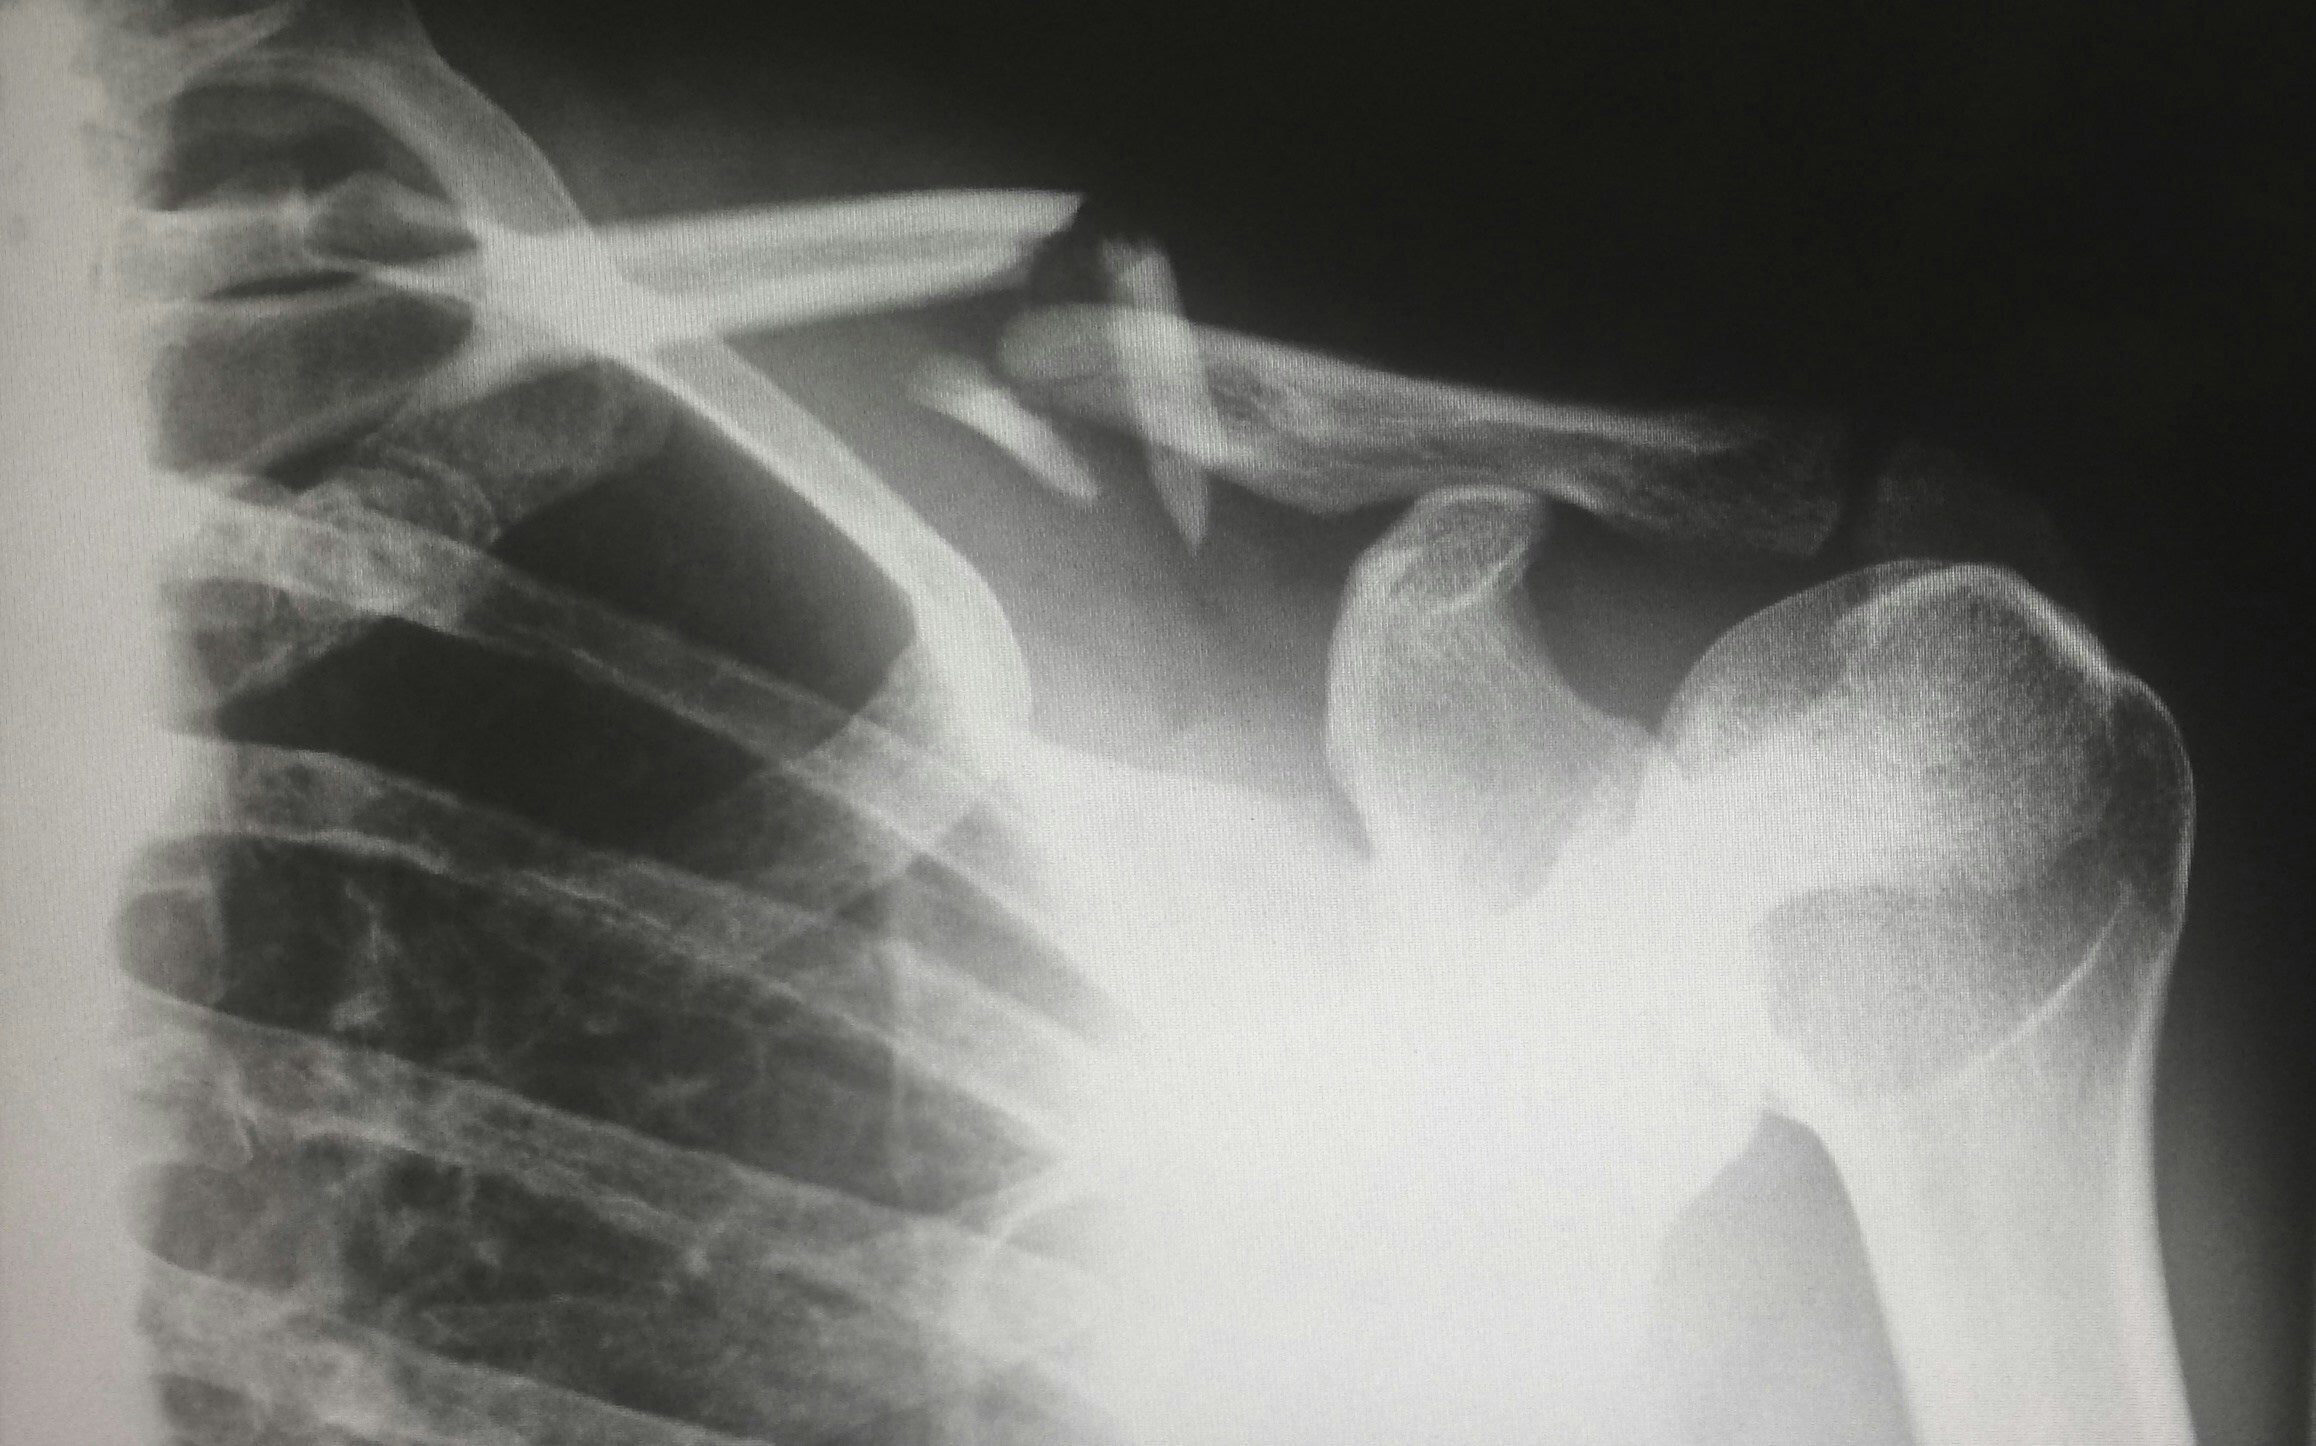

想象一下,如果你有一部手机,它能让你透视墙壁。据IEEE Xplore(通过CBS 新闻)报道,一个已经筹备了 15 年的项目正在继续推进。该项目的目标是开发一种芯片,让智能手机用户能够像 X 射线一样透视固体表面。但后者对人体有害,因此这款手机实际上不使用 X 射线,而是使用 200 GHz 至 400 GHz 范围内的信号。

到目前为止,测试表明该技术可以穿透灰尘、浓雾和光线通常无法穿透的空气中的颗粒。在最近的一次测试中,研究人员能够透过纸板看东西。在我们对此感到兴奋之前,报告指出,智能手机用户可能只需要几年时间就能利用千兆赫信号看穿墙壁和物体。

研究人员正在研究让智能手机用户能够透过固体物体观察的技术。

最终,装有这些芯片的智能手机将能够查看信封和包裹内部。医院还可以使用此类设备检查患者的水分含量。目前,该技术要求手机要查看的物体距离设备不超过一英寸。这可以防止小偷站在离目标较远的地方,以便秘密使用该技术查看某人的手提箱或包以发现个人信息。